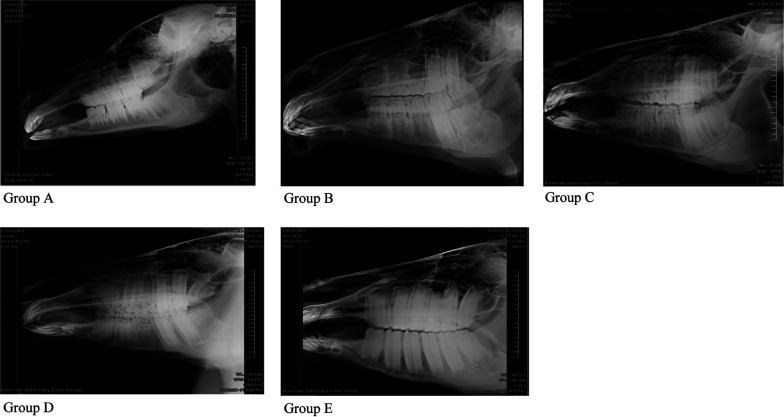

Dareshuri马是伊朗法尔斯省的主要品种。虽然影响上颌颊齿和上颌窦的疾病相对常见,但关于这些结构在不同年龄的尺寸和关系的基础数据有限。考虑到年轻马的头部在成熟过程中发生了显著的解剖学变化,本研究旨在评估上颌颊齿在吻侧和尾侧鼻窦(分别为RMS和CMS)内的位置和解剖关系的年龄相关变化,以及在其生长过程中单个鼻窦室的长度和高度的变化。研究人员对29匹年龄在4个月至5岁之间的健康活马的头部进行了放射线照相,并使用EConsole1放射线照相查看器软件(V.3, 2017, DRTECH Europe GmbH, Schwalbach am Taunus,德国)进行了分析。统计分析显示,整个研究中唯一显著的变化是CMS长度的增加(4.075±0.99 cm; SE),这在3岁以下的马中更为显著。在不到1岁时,上颌窦中唯一存在的牙齿是M1。1 ~ 2岁时,M2进入上颌隔室;PM4在2 ~ 3岁进入RMS, M3在3 ~ 4岁进入CMS。最终,在4 ~ 5岁时,PM3、M1和M2出现在RMS中,M2和M3出现在CMS中。本研究结果对临床上颌面部疾病的诊断和治疗具有一定的参考价值,并可作为进一步解剖研究的参考。

Dareshuri horses are the predominant breed in Fars Province, Iran. Although disorders affecting their maxillary cheek teeth and maxillary sinuses are relatively common, limited fundamental data are available on the dimensions and relationships of these structures at different ages. Given the significant anatomical changes in the heads of young horses as they mature, this study aimed to evaluate age-related changes in the position and anatomical relationships of individual maxillary cheek teeth within the rostral and caudal maxillary sinuses (RMS and CMS, respectively), as well as changes in the lengths and heights of individual sinus compartments during their growth. Radiographs were performed on 29 heads of live, healthy horses aged between 4 months and 5 years and were analyzed using the EConsole1 Radiography Viewer software (V.3, 2017, DRTECH Europe GmbH, Schwalbach am Taunus, Germany). Statistical analyses revealed that the only significant change throughout the study was an increase in the length of the CMS (4.075 ± 0.99 cm; SE), which was more significant in horses up to three years old. At less than 1 year old, the only tooth present in the maxillary sinus was M1. At 1-2 years old, M2 was observed entering the maxillary compartments; PM4 entered the RMS at 2-3 years old, and M3 entered the CMS at 3-4 years old. Eventually at 4-5 years old, PM3, M1, and M2 were present in the RMS, and M2 and M3 were present in the CMS. This information should be of value in the diagnosis and treatment of Dareshuri maxillofacial disorders and used as a reference for further anatomical investigations.